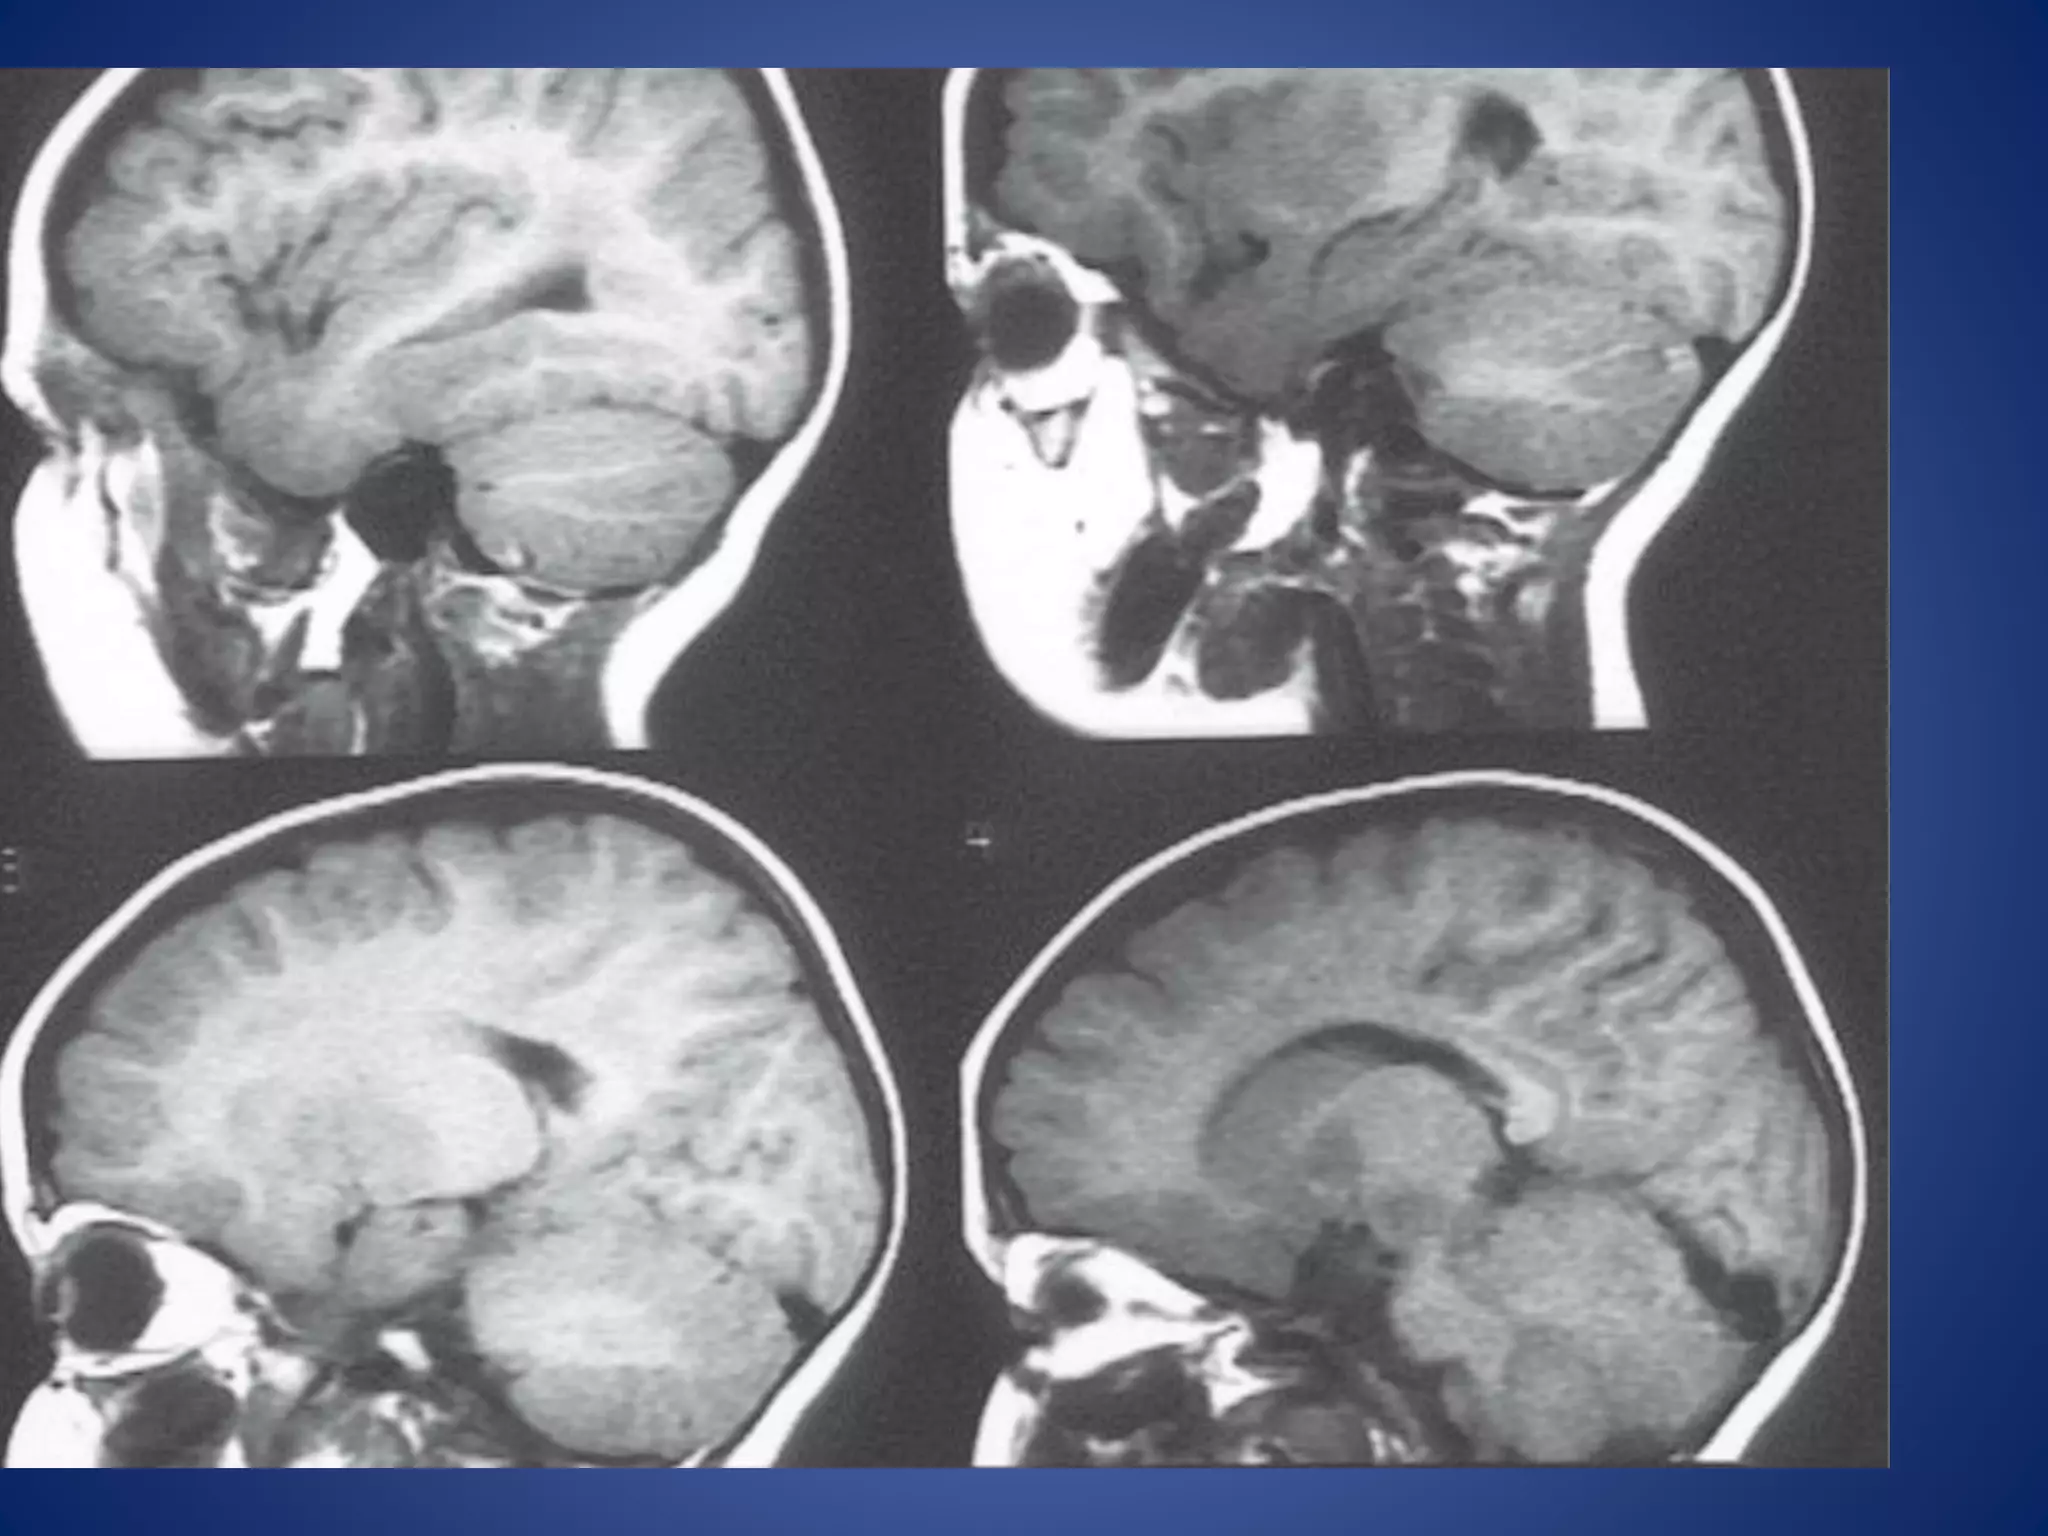

1.Truncation artifact

• Appearance: appears as a banding artifact at the

interface of high and low signals. It creates the low

intensity band running through high intensity areas.

• Causes:

• results from undersampling of data (too few k-space

lines are filled) so that interfaces of high and low signal

are incorrectly represented on the image.

• is most common when tissue is still producing a high

signal at the end of data collection or when the peak of

the echo is not centered in the middle of the sampling

window.